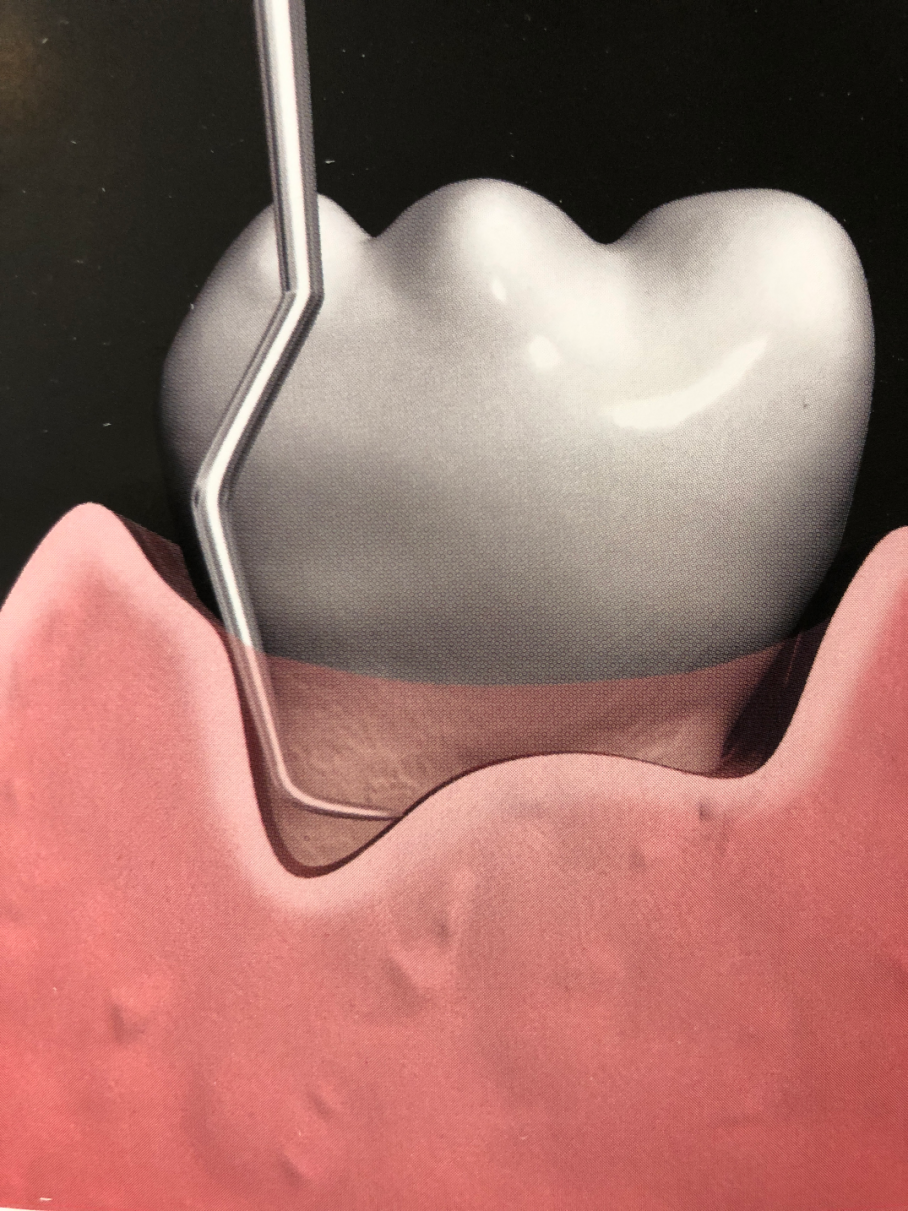

En la mayoría de los pacientes una vez finalizada la terapia periodontal no quirúrgica nos enfrentamos a la difícil realidad: muchas bolsas no han reparado y por sus características no van a reparar. Este curso te ayuda a conocer y seleccionar la terapia indicada.